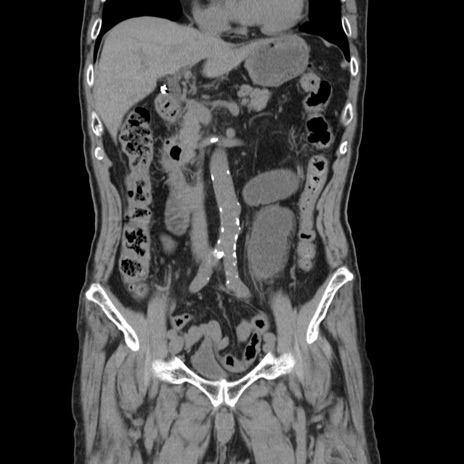

症例24(冠状断像)

【症例】80歳代男性

【主訴】左側腹部痛、嘔吐

【現病歴】本日早朝より左腹部に痛みあり。昼頃嘔吐認めたため、救急要請。

【既往歴】直腸癌(Mile手術)、胆摘

【身体所見】意識清明、BT 35.9℃、BP 221/93mmHg、SpO2 97%(RA) 、腹部:左ストーマ周囲に限局性の腹部膨隆あり。 膨隆部自発痛・圧痛あり・軟。

【データ】WBC 7700、CRP 0.09